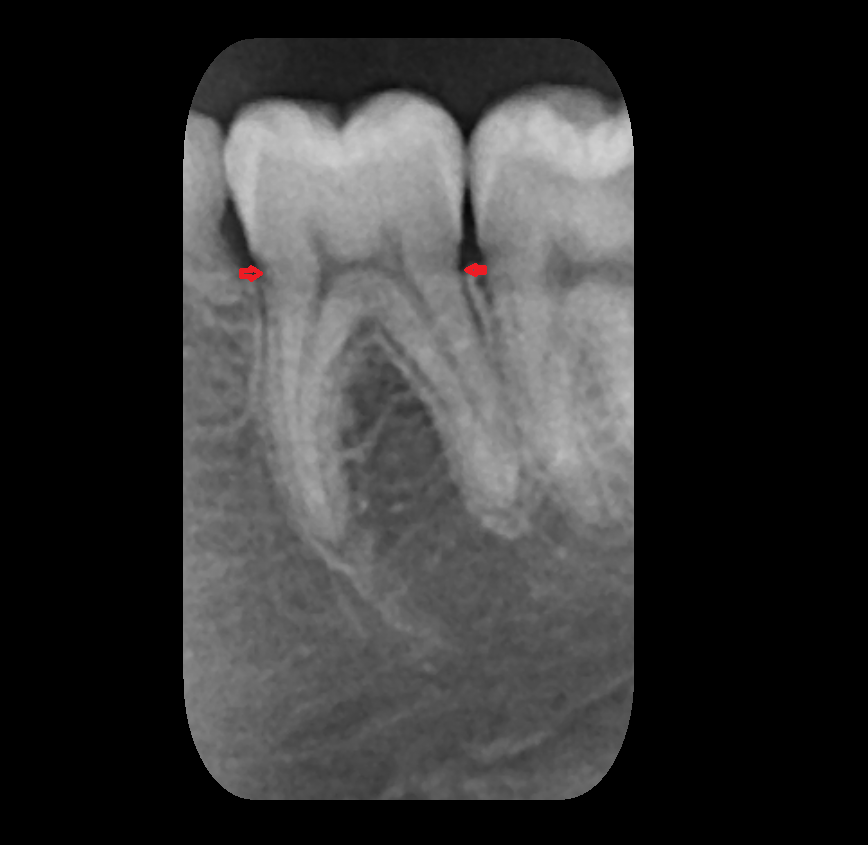

- Root of lower molar tooth

- Lower molar apical foramen

- Upper premolar apical foramen

- Root of upper molar tooth

- Root canal of upper molar tooth

- Dental pulp of upper molar tooth

- Enamel of lower molar tooth

- Enamel of upper molar tooth

- Dental pulp of lower molar tooth